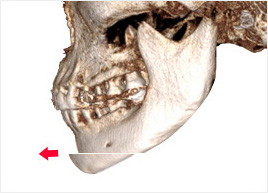

턱 끝 신경선을 피해서 턱 끝 뼈를 절골

합니다.

절골한 턱 끝을 수술 계획에 따라 앞으로

이동시킵니다.

절골한 턱 끝을 고정핀으로 고정시켜 주고

봉합합니다.